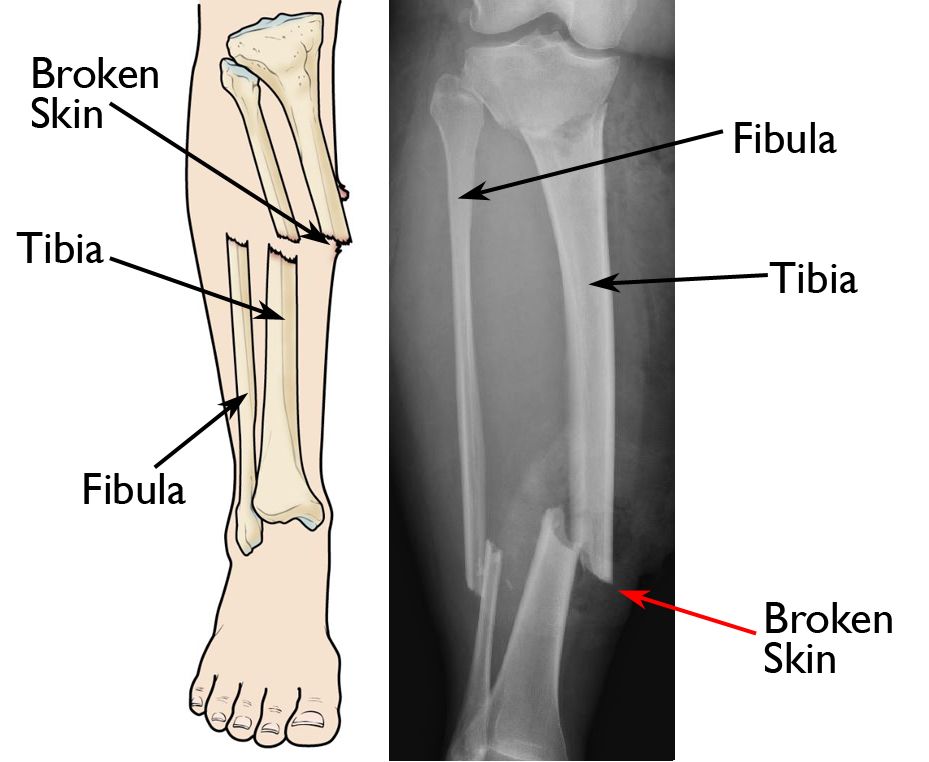

It can be anything from a small crack to a separated bone that causes it to move out of place. There are different types of fractures and symptoms include pain swelling and discoloration of the skin around the injured area. Fractures and bone healing - Learn of fractured bones bone fracture types how to heal broken bones fracture treatment symptoms healing and causes.

Spiral Fracture Healing Time Tibia And Fibula